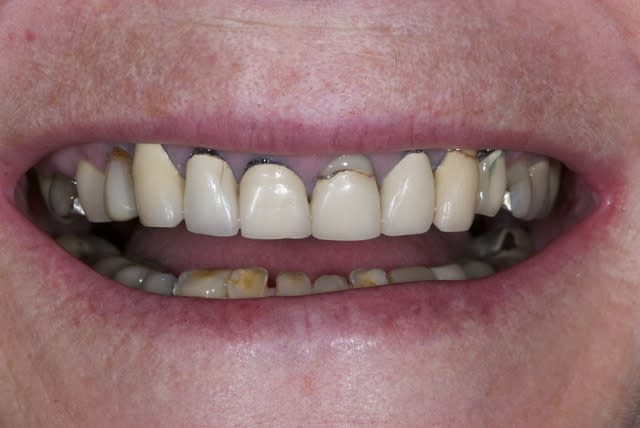

La demande concerne la réhabilitation esthétique du bloc incisif supérieur.

On ne parlera pas de bruxisme, de dvo, de gouttière et de réhabilitation globale pour diverses raisons, seule le traitement esthétique de 14 a 24 nous concerne ici et ses différentes solutions pour le traiter.

A part 24 rien ne bouge, pas de douleurs, pas de problème paro, juste un problème esthétique sur ses vielles ccm.

on fait juste des nouvelles ccm ou on peut faire mieux?